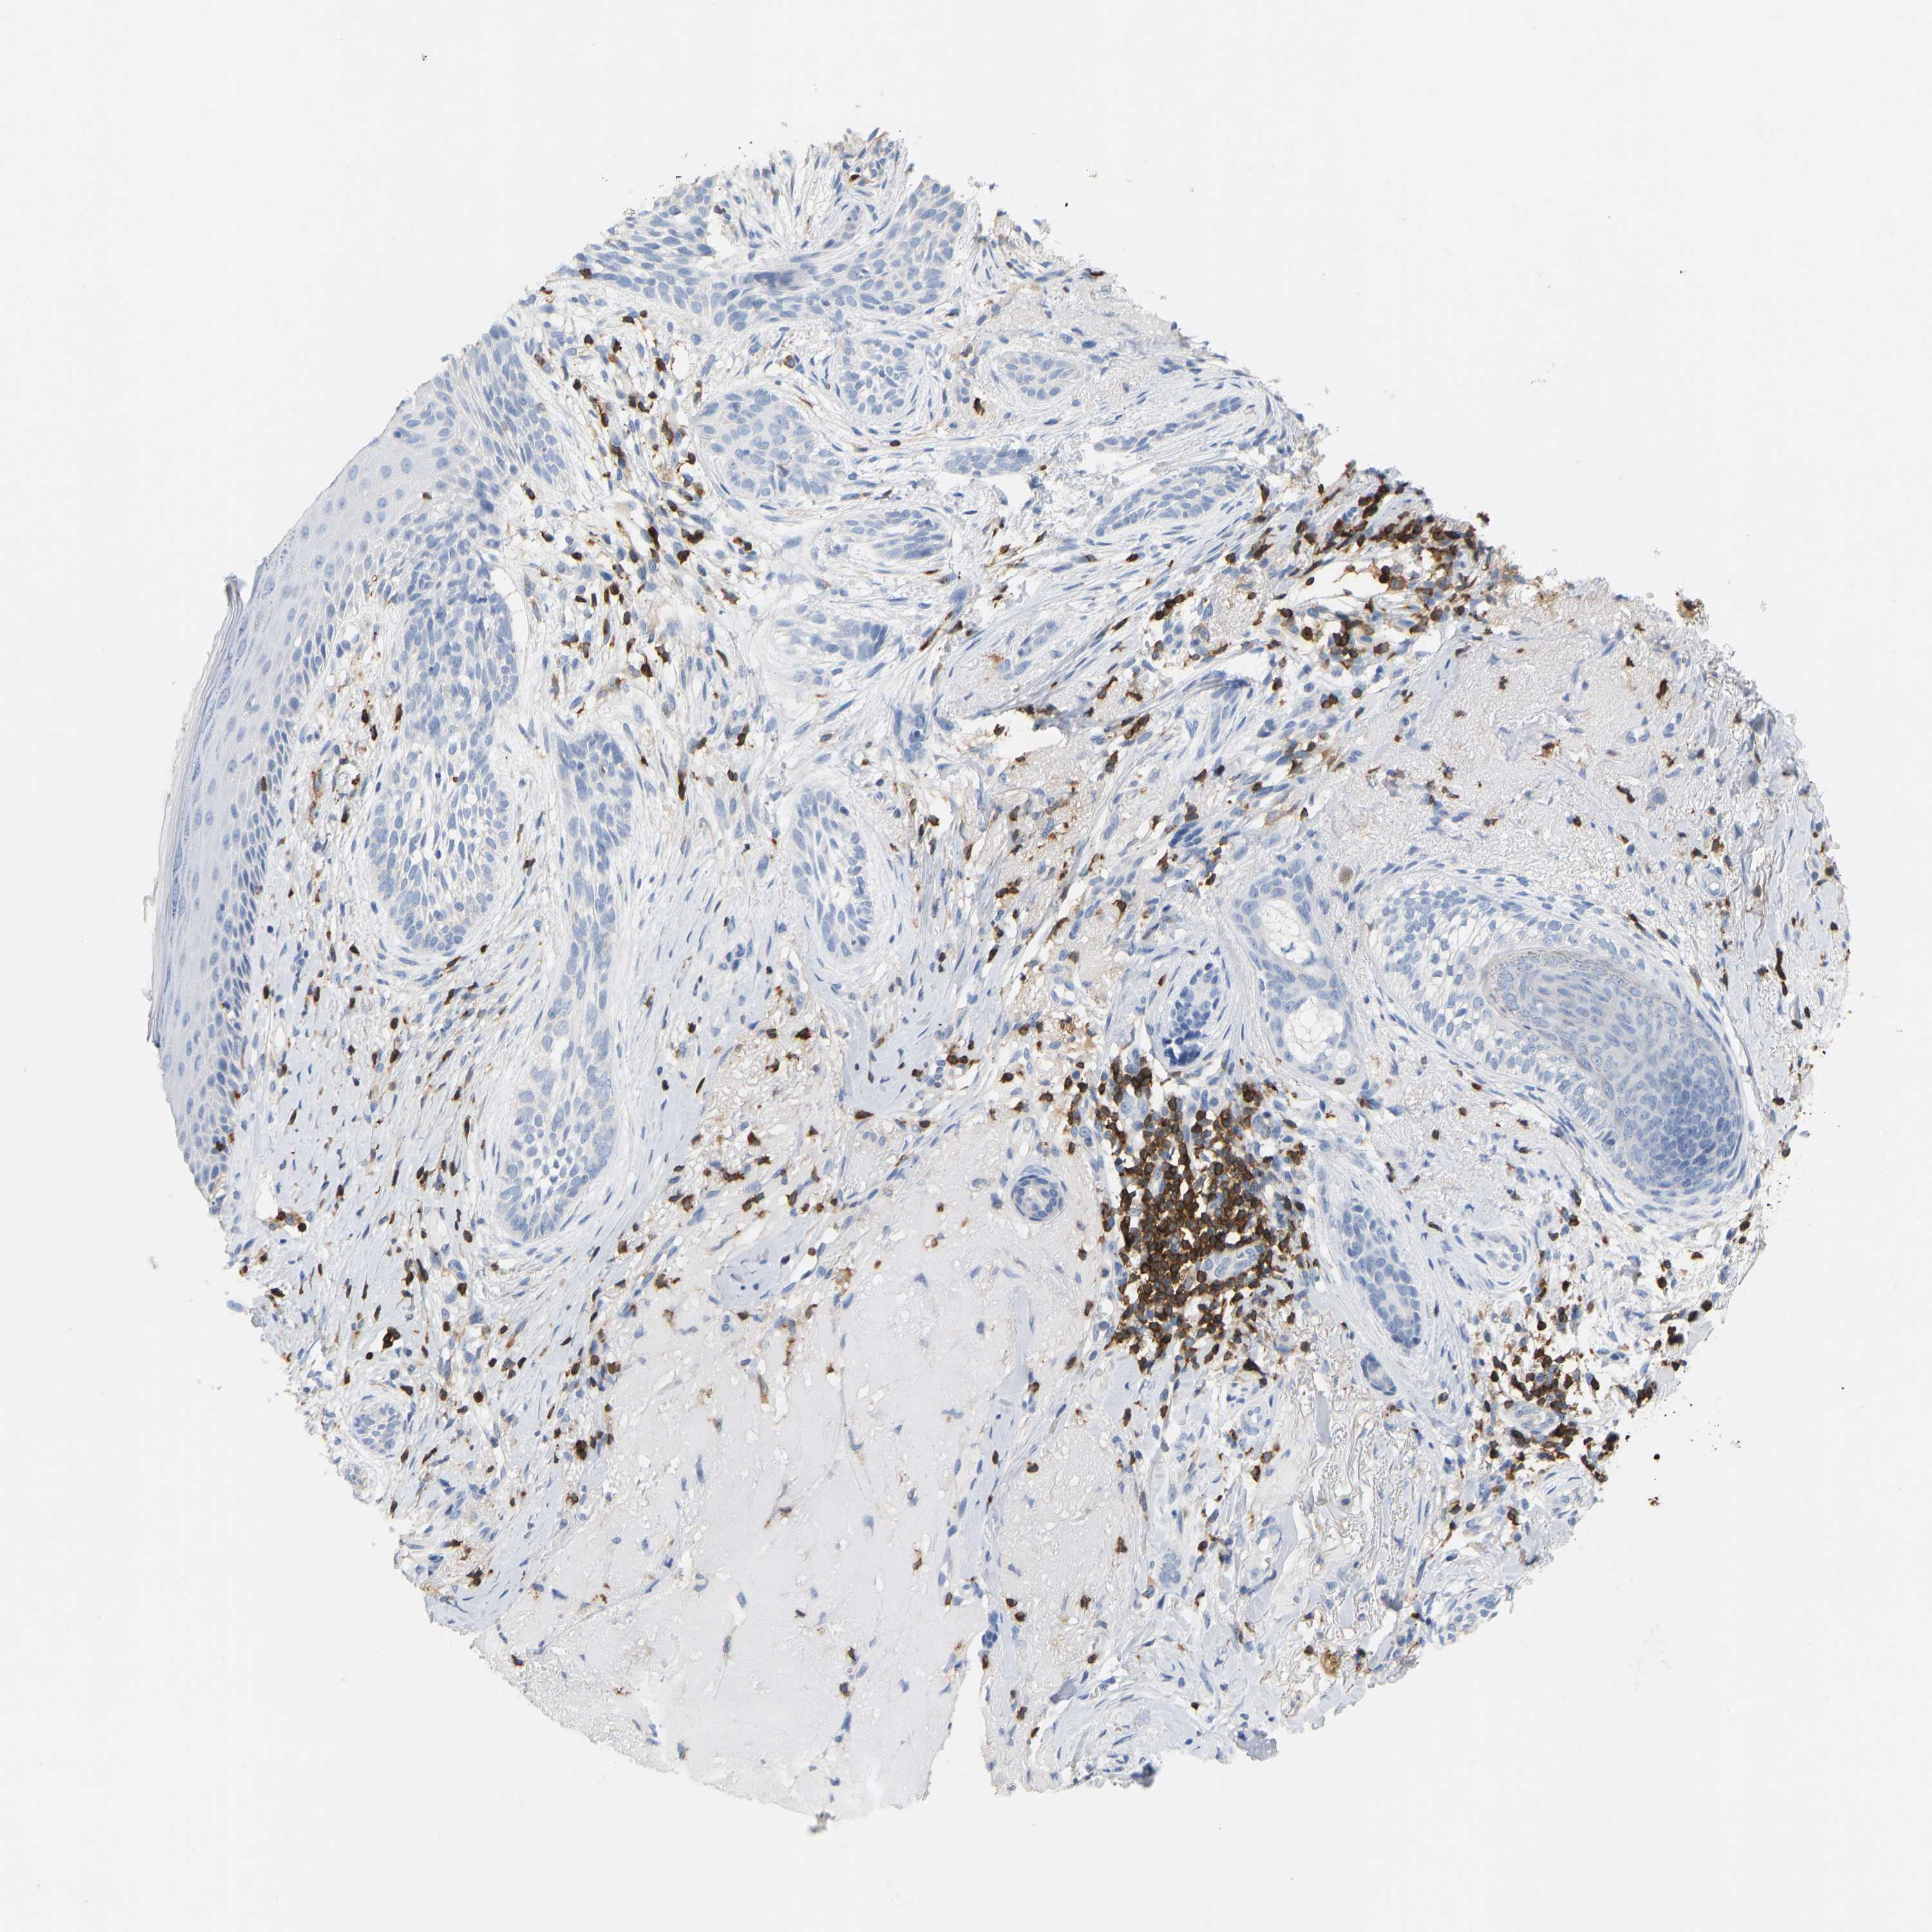

SKIN CANCER - Protein expressioni

A mouse-over function shows sample information and annotation data. Click on an image to view it in a full screen mode. Samples can be filtered based on level of antibody staining by selecting one or several of the following categories: high, medium, low and not detected. The assay and annotation is described here.

Each image is clickable and will lead to virtual microscopy that enables deeper exploration of all samples and also displays staining intensity scores, fraction scores and subcellular localization as well as patient and tissue information for each sample.

Antibody HPA019536

Squamous cell carcinoma, NOS